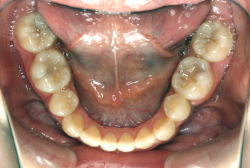

「左奥歯でものが噛めない」という主訴で来院したケースです。診断の結果、基本的には「叢生」という隙間が足りないと言うことが原因の凸凹症例でしたが、左下の乳歯が高校生になってもまだ残存している状態で、そのせいで噛み合わせが極端に悪くなっていました。

検査の結果、乳歯の下には後継ぎの永久歯が先天的に欠如していました。配列の凸凹が厳しく非抜歯で矯正することは難しく、仮に無理をして非抜歯治療をしても後々「後戻り」が懸念されることから、このような症例の場合は通常、上下顎左右第一小臼歯を抜歯させていただくのですが、左下は乳歯を抜歯して、第一小臼歯は残すことにしました。これで結果として、小臼歯部を上下左右で一つずつ減らしたのと同じ状況になります。治療後は歯並びが綺麗になっただけでなく、噛み合わせ的にも正しい状態が確立しています。

このように、先天的に永久歯が足りないという症例は最近増えています。親知らずはなくても特に問題になりませんが、その他の歯が足りないと言うのは審美的にも機能的にも重大な障害となります。しかし、矯正治療を正しく行えば、結果として歯がすべてあった場合と全く同じ仕上げにすることも可能です。